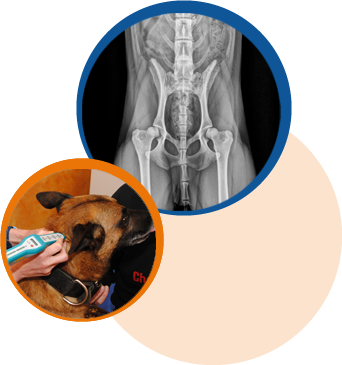

Anwendungsgebiete

• Skeletterkrankungen

z.B. Hüftgelenks- und Ellenbogendysplasie, Wirbelsäulenerkrankungen, OCD, Frakturen sowie Patellaluxation

• Degenerative Erkrankungen

z.B. Arthrose, Spondylose

• Neurologische Erkrankungen

z.B. Bandscheibenvorfall (Dackellähme), Cauda-Equina-Kompressionssyndrom, Wobbler-Syndrom, Ataxien, Lähmungen

• Muskuläre Erkrankungen

z.B. Muskelverspannungen, Kontrakturen, Rupturen, Muskelatrophien

• Bänder- und Sehnenverletzungen

z.B. Kreuzbandriss, Sehnenentzündungen, Sehnenrupturen

• Weitere Indikationen

z.B. vor und nach Operationen, Ödeme, begleitende Maßnahme bei chronischen Schmerzpatienten, Verbesserung der Beweglichkeit bei älteren Tieren, Hilfe bei der Gewichtsreduktion, Unterstützung der Leistungsverbesserung, Prophylaxe bei Sport- und Arbeitshunden, Wellness